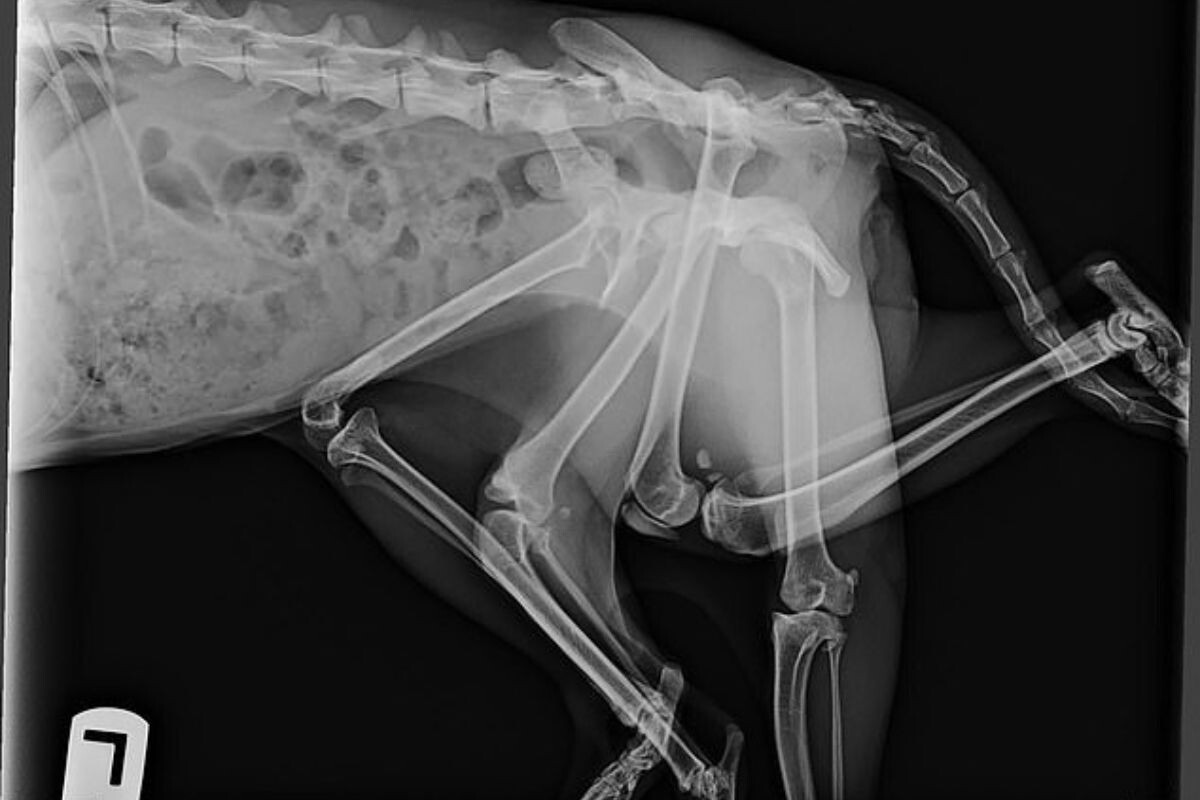

Специалисты считают, что у кошки внутриутробно начал развиваться близнец, частично слившийся с основным плодом — так называемый паразитический близнец. Это крайне редкое явление, при котором фрагменты второго эмбриона остаются присоединёнными к телу основного и могут проявляться в виде дополнительных конечностей, органов или участков скелета. В ветеринарной практике такие случаи зафиксированы у разных видов, но встречаются чрезвычайно редко.

Снимок Битси. Фото: Furget Me Not Animal Rescue in Edmonton

У Битси из задней части тела выступали две лишние лапы и дополнительный фрагмент таза. В итоге у неё было шесть конечностей, три из которых не функционировали и причиняли дискомфорт. Из-за этого кошке было трудно передвигаться, ложиться и даже доставать до своей миски с едой.